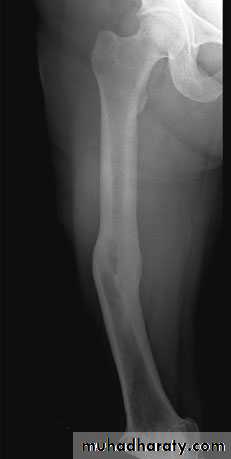

Radiological diagnosis;

The fr line can be shown by a good x-ray exam. specially with application of the role of two, the fr line can be seen and we can describe the fr site, shape and displacement exactly.

Hypertrophic non-union gives the radiological appearance of maintenance of the fr line with extensive callus proximal and distal to it, also abnormal position of the fragments may be seen. The appearance sometimes refereed to as elephant foot or hours hoof appearance.